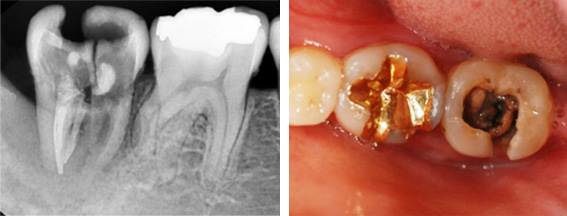

1년전 다른 치과에서 보철치료를 받은 부위에 지속적인 통증과

잇몸 염증으로 내원, 기존 보철물 수복시 신경관을 제대로 치료하지 못하여 염증이 재발된 상황이었습니다. 고운미소에서는 기존 포스트를 제거하고 오염된 부위에 약재를 삽입하여 염증을 제거하는 신경치료를 시행하였습니다.

지속적인 통증과 잇몸염증

기존 포스트 제거

근관내 약재 삽입

치근단 부위 회복

염증을 제거하는 신경치료 후 치근단 부위가 빠르게 회복되어 깔끔하게 신경치료를 완료하고 크라운 보철물을 씌웠습니다. 신경치료를 받은 치아는 약해져 있기 때문에 크라운 보철물로 씌워주어 세균 감염을 예방해야 합니다.